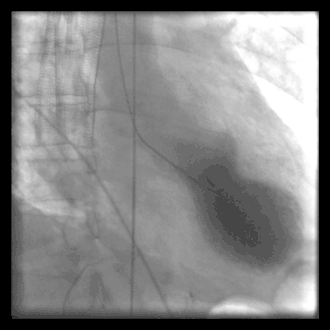

A Stress-Kardiomyopathie

B Normalperson

Die Röntgenaufnahme der Thoraxorgane ist unauffällig oder zeigt eine sogenannte Lungenstauung („Wasser in der Lunge“) als Folge der Herzinsuffizienz. Bei der Echokardiografie ist die für das Tako-Tsubo-Syndrom typische Bewegungsstörung (Kontraktionsstörung) der linken Herzkammer oft nachweisbar, das apical ballooning. Diese auch bei der Laevokardiografie im Rahmen einer Herzkatheteruntersuchung nachweisbare Kontraktionsstörung des linken Ventrikels macht sich als oft eindrucksvolle Unbeweglichkeit (Akinesie) oder gar als paradoxe Beweglichkeit (Dyskinesie) der Herzspitze bemerkbar, die Ähnlichkeit mit einem Aneurysma aufweisen kann.

Im Unterschied zum Herzinfarkt ist allerdings bei der Koronarangiografie keine Verstopfung der Herzkranzgefäße nachweisbar. Erst dieser Befund der Herzkatheteruntersuchung erlaubt die zuverlässige Abgrenzung zum Herzinfarkt.